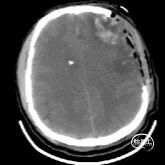

辅助检查:入院当天头部CT示:双侧额顶叶、左侧颞叶脑挫裂伤,最大截面约3.05×2.30cm,蛛网膜下腔出血。